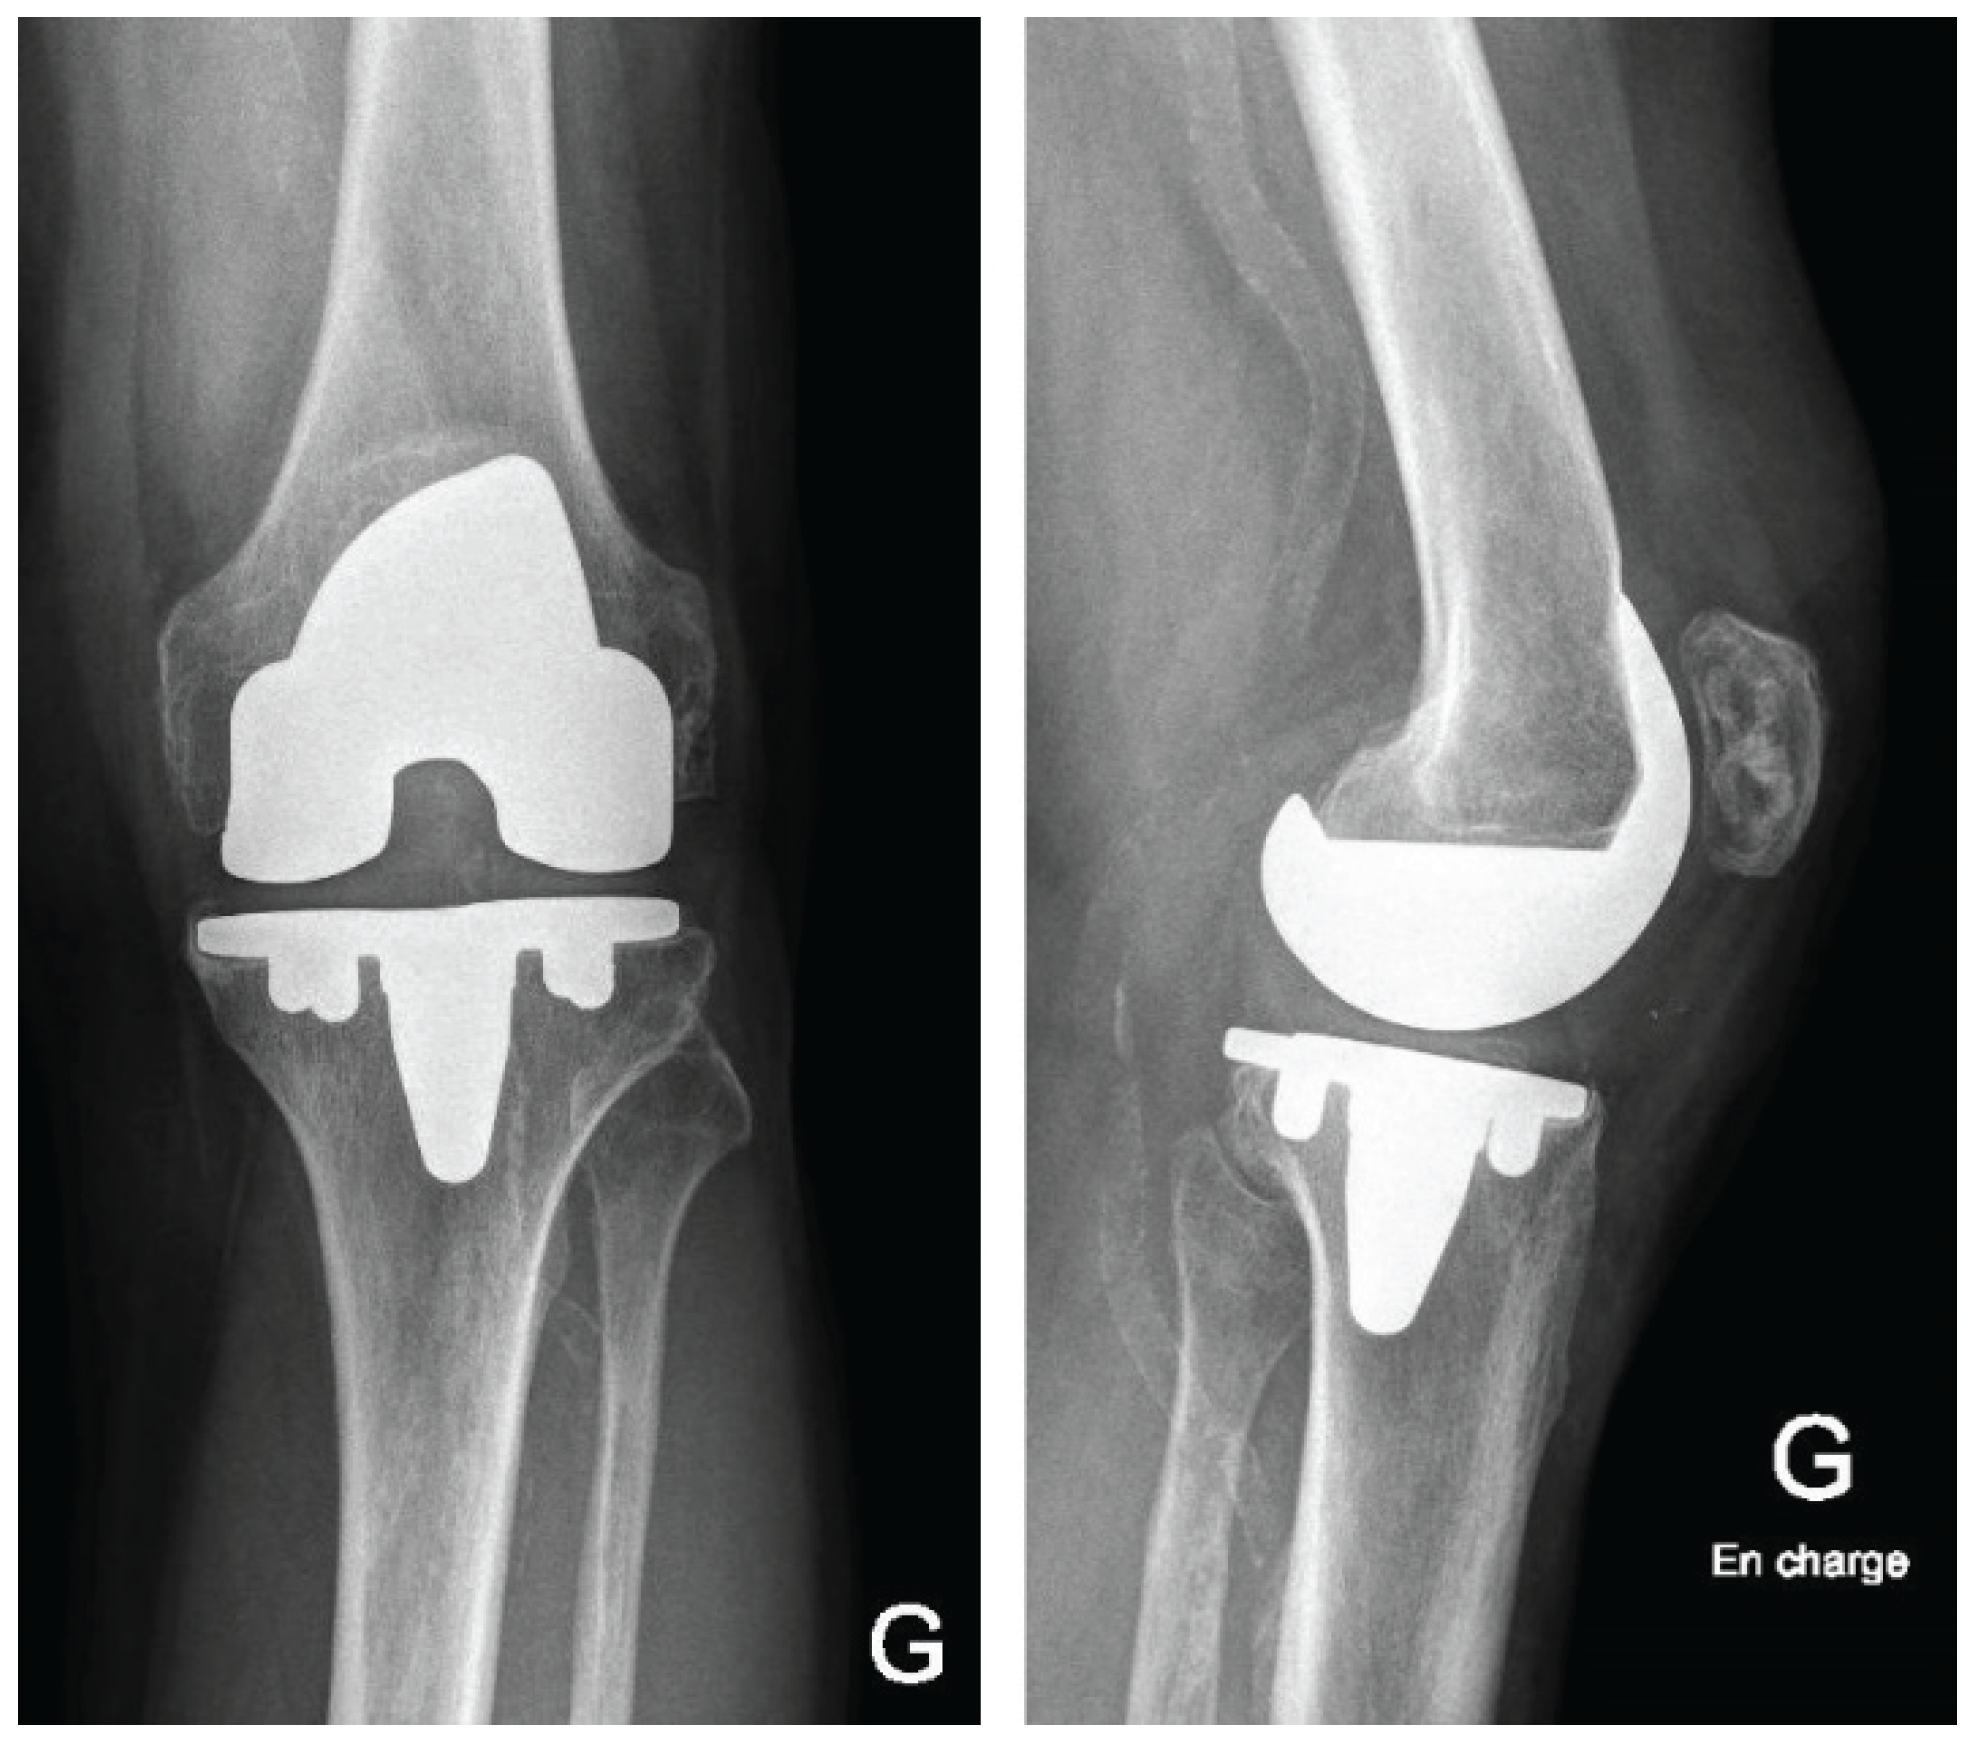

Postoperatively, patients follow a standardized rehabilitation program encouraging early mobilization and full weight-bearing as tolerated. Deep venous thrombosis prophylaxis and early quadriceps activation exercises are initiated according to institutional protocol. Postoperative radiographs of the knee and full-length lower limb are obtained to confirm accurate component positioning (Figure 7).

Figure 7. Radiographic comparison of preoperative and postoperative component positioning and alignment (a) Preop AP view; (b) Preop Lateral view; (c) Postop AP view; (d) Postop Lateral view.